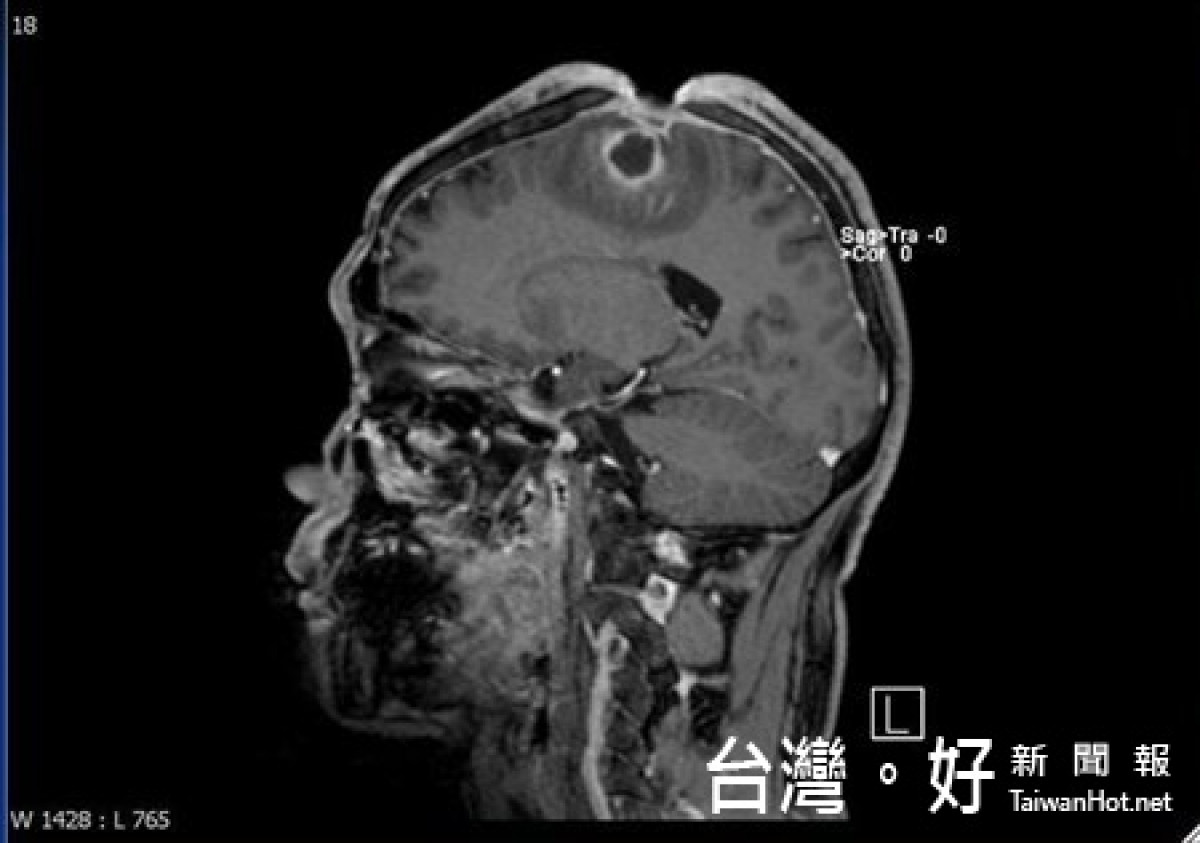

結果陳先生竟然在自己的腦袋挖出5×3×2公分的傷口,這一年期間,他生活、上班一切都沒有異狀,只是習慣用戴帽子的方式將傷口遮住,所以家人同事都沒有發現異狀,結果因為傷口感染,出現類似中風的狀況,家人在協助送醫之後,才知道陳先生竟然將自己的頭骨,腦膜都給挖破了。

傷口因為感染嚴重,醫生除了使用抗生素治療了3個月,還進行清瘡和顱骨重建手術,潘建志表示,這類患者在治療時必須先建立雙方信任關係,才能說服病人進一步治療。病人也因為腦部感染的後遺症,導致右側肢體無力,而復健長達半年的時間。